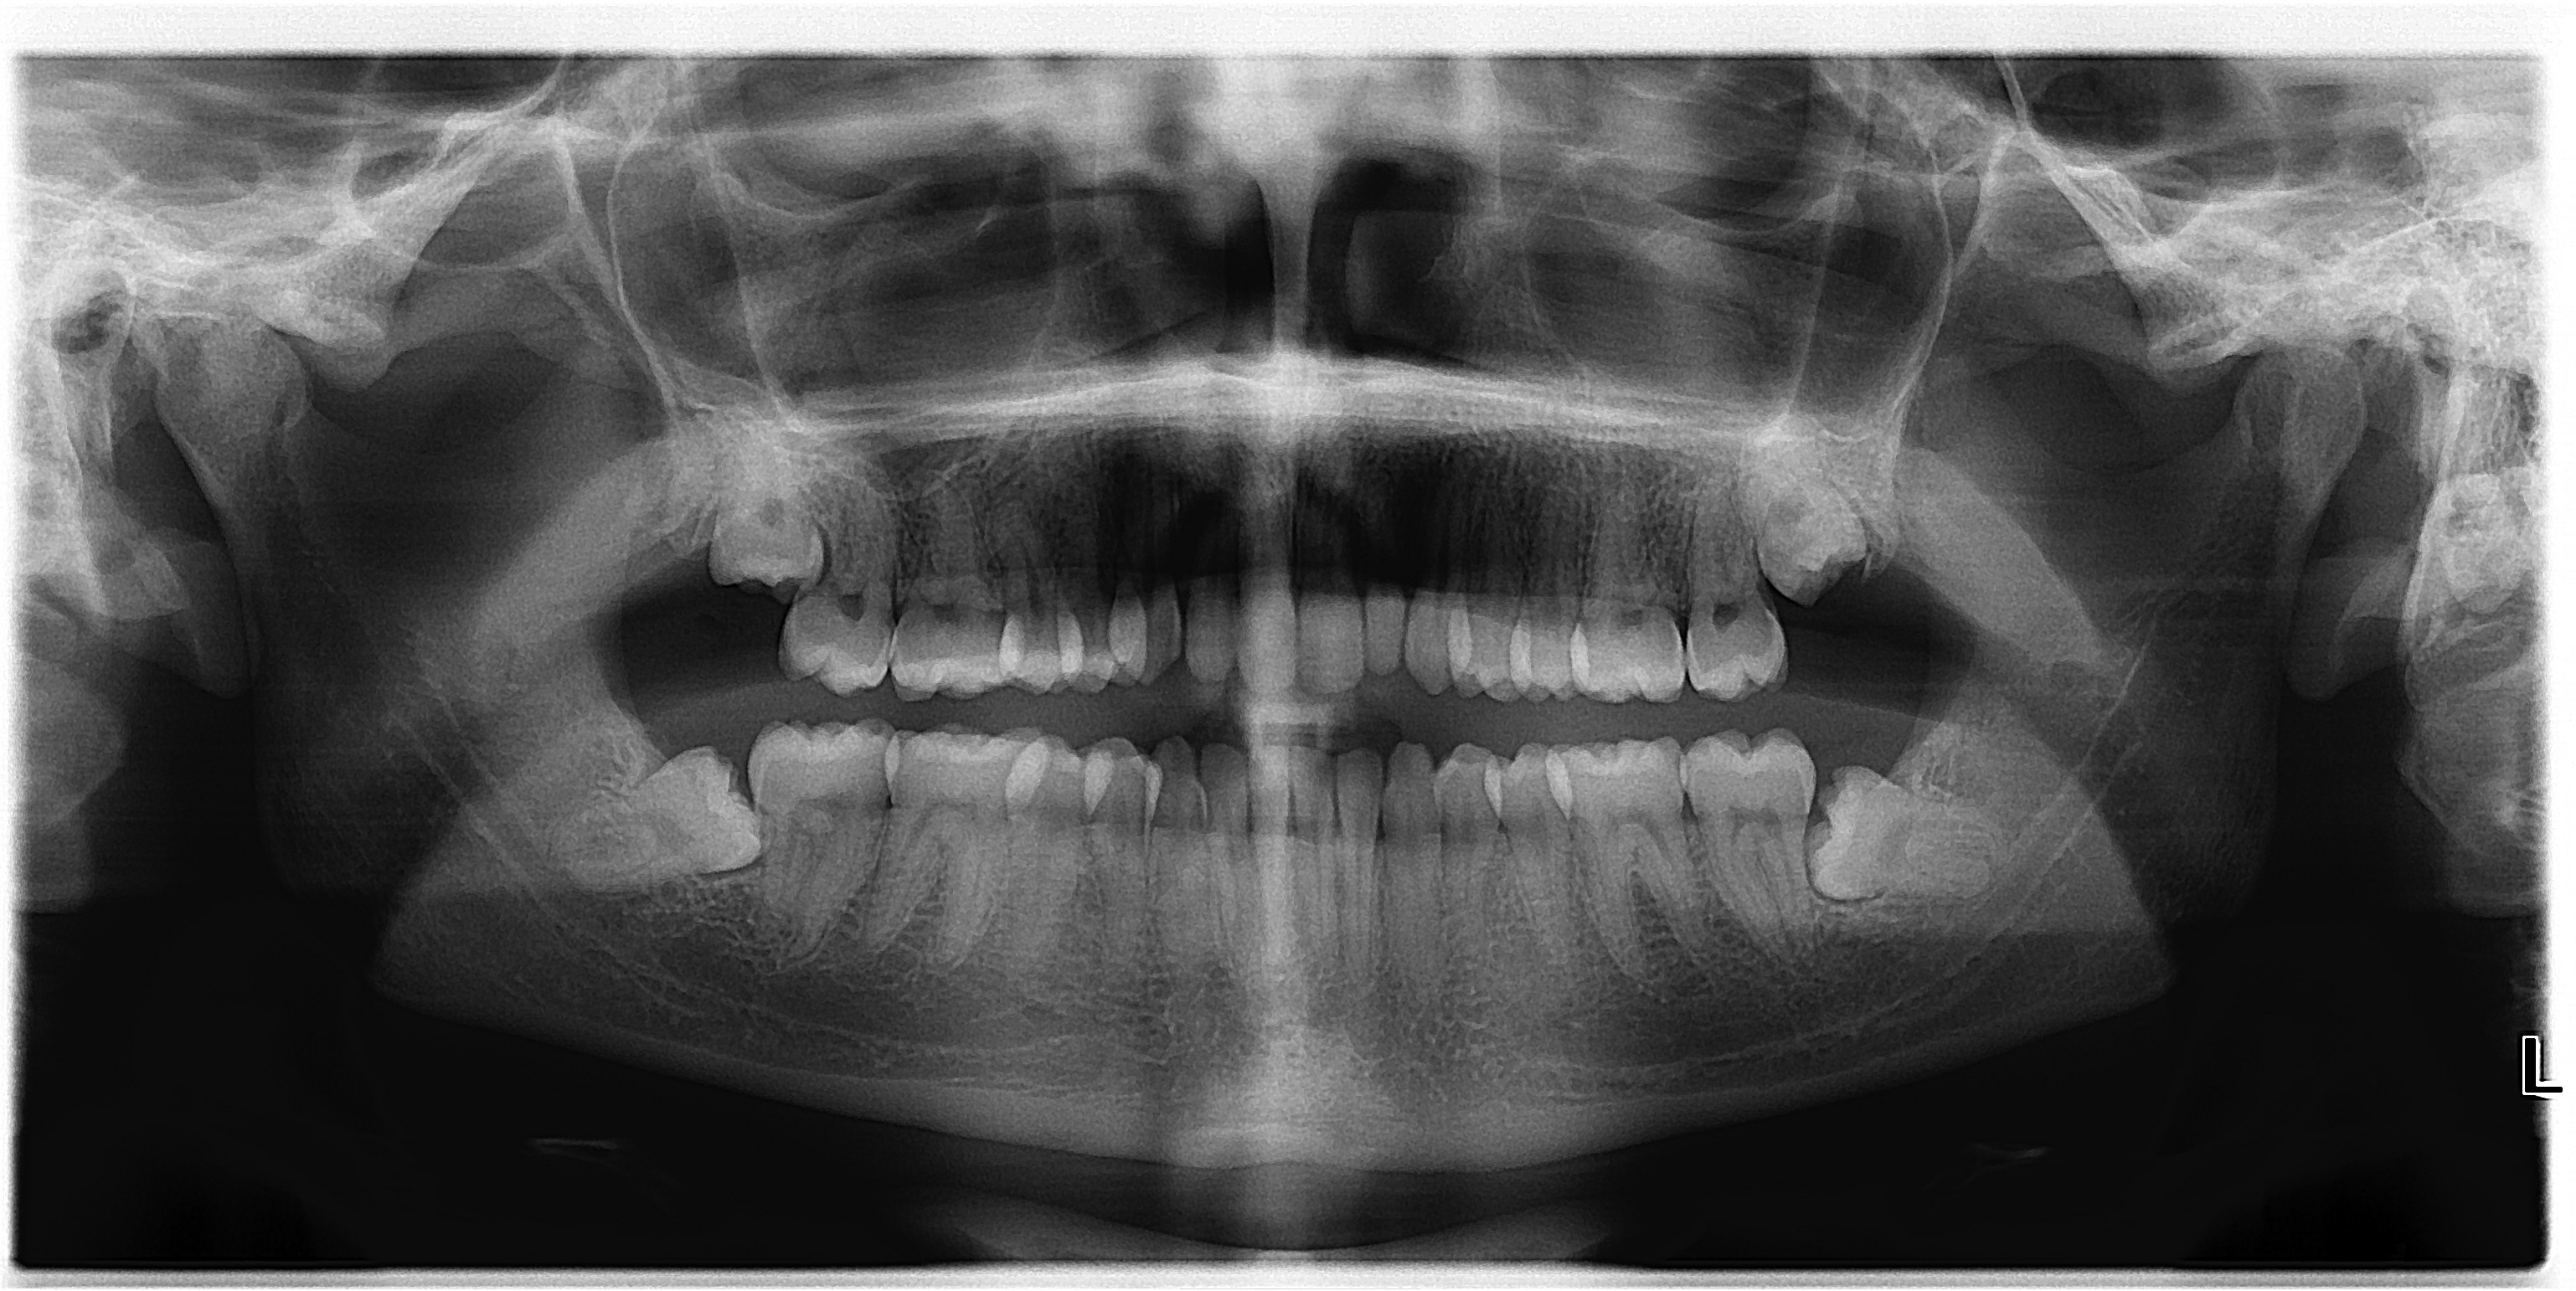

From www.drkyleasmith.com

From www.primalpictures.com

The Anatomy of Wisdom Teeth From Primal Roots to Modern Dentistry What Is A Wisdom Teeth Made Of You’d need some pretty powerful chompers to cut up your food, right? A 'wisdom' tooth is a third molar tooth. Wisdom teeth come in at the very back of our mouth, with one at the end of each row of teeth. Wisdom teeth are the third and final set of molars that most people get in their late teens or. What Is A Wisdom Teeth Made Of.